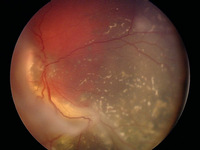

Two large retinoblastoma foci in the left eye; note the associated subretinal seeding

Personal collection of Dr Timothy Murray